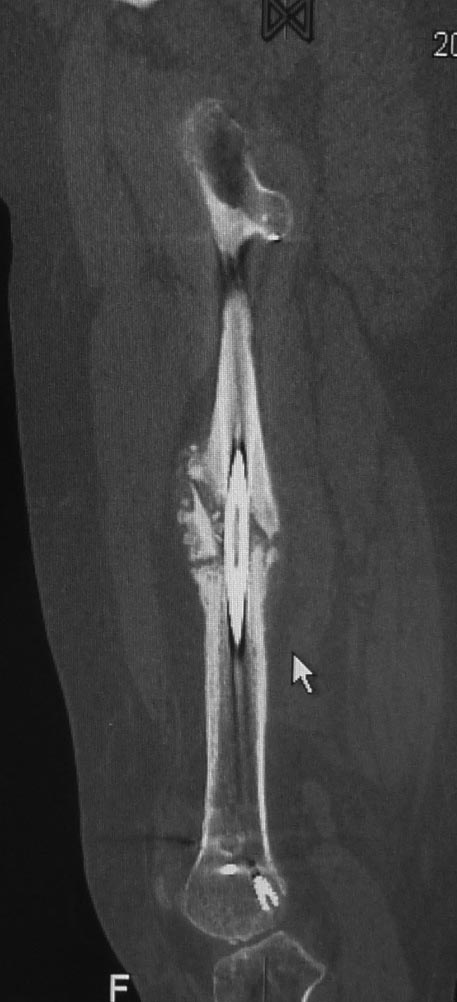

Уважаемые коллеги. Хотелось бы выслушать мнения и советы по представленному случаю. Пациент 42 лет, вес 130 кг, рост около 160 см, сахарный диабет в легкой форме (впервые выявлен после травмы). Травма в феврале 2011 г. - упал с мотоцикла на отдыхе за рубежом. По возвращении в Россию был прооперирован в несколько этапов: в марте 2011 г. - остеосинтез обеих костей правого предплечья пластинами по поводу открытого перелома; интрамедуллярный остеосинтез правого бедра; остеосинтез проксимального конца правой большеберцовой кости. В апреле 2011 г. был доставлен 1 блокирующий винт в дистальное отверстие гвоздя и выполнена пластика крестообразных и наружной боковой связок левого коленного сустава. В феврале 2012 г. были удалены фиксаторы с проксимального конца правой большеберцовой кости и выполнена пластика крестообразных и наружной боковой связок правого коленного сустава. За это время пациент смог начать ходить, сначала с костылями, а затем - без дополнительной опоры. Летом 2013 г. решил укрепить ноги с помощью подъемов пешком на пятый этаж. В результате - усталостная рефрактура правого бедра и перелом интрамедуллярного гвоздя. 09.09.2013 - реостеосинтез латеральным бедренным гвоздем с пластикой костной аутостружкой + СhronoS. Сейчас, через 6 мес после операции, может ходить без дополнительной опоры, периодически беспокоит болезненность в области правого бедра. На сегодняшних КТ - отсутствие признаков консолидации. Нужно ли что то делать и, если да, то что? Рассматриваемые варианты: повторная костная пластика дефекта; доставить блокирующие винты (самый проксимальный винт был удален через 3 мес после операции). Еще раз менять гвоздь не хотелось бы. На представленных снимках: бедро в 2011 г., через несколько мес после операции; в 2012 г., на стадии консолидации; со сломанным гвоздем; сразу после повторной операции (3 рентгенограммы). Все КТ - сегодняшние. Заранее спасибо за ответы.

ждать-не ждать? Срочности нет, подождать можно, но активно, т.е. оценить клиническую и рентгенологическую динамику: два месяца назад, сейчас и еще через пару месяцев. Уменьшатся боли, появится более убедительная мозоль - ждите и наблюдайте дальше. Отсутствие положительной динамики можно приравнять к отрицательной динамике. Очевидно, что здесь имеют место быть обе проблемы: биологическая -мозоль слабая и механическая - тонкий гвоздь, недостаточная стабильность. Тогда -удаление, рассверливание (очень аккуратное, по 0.5 мм шаг, острыми фрезами, чтобы не пожечь кость - кортикал толстый и довольно прочный). Для 130 кг диаметр гвоздя минимум 12 мм, лучше больше. Здесь можно и 14мм гвоздь взять и блокировать дистально винтами 6,0 мм. Открывать перелом и пытаться делать еще пластику экстрамедуллярно не стоит. Рассверливания будет достаточно.

Источник проблем - отсуствие рассверливания, тонкий гвоздь и костная пластика. При интрамедуллярном остеосинтезе (относительная стабильность) класть кусочки кости открыто бесполезно - не приживут. Только еще ухудшили кровоснабжение концов. А что там с длиной сегмента? Если длина не потерялась - реостеосинтез с рассверливанием, как А.Семенистый написал. Если укорочение - удалить, остеотомия на другом уровне и дистракиця, на стыке - компрессия, и по достижении нужной длины - заштифтовать с рассверливанием, аппарат снять только после запирания гвоздя.

Костная пластика делалась стружкой из фрагментов большого вертела: верхний конец предыдущего гвоздя был погружен в него на пару см (первый гвоздь ставился не у нас, я только доставил второй дистальный блокирующий винт)и гранулами СhronОs. Учитывая совершенно необъятные размеры бедра, удаление сломанного гвоздя получилось достаточно травматичным. Пришлось широко открываться проксимально, на уровне перелома и дистальнее, чтобы сформировать окошко для выбивания дистального отломка гвоздя (дистальный конец гвоздя не имел отверстия). После операции около месяца собиралась жидкость в области большого вертела (серома), на фоне пункций постепенно ушла. Поэтому и хотелось бы избежать еще одного вмешательства на уровне большого вертела.

А открытая операция на диафизе приведет к ухудшению без того нарушенного кровоснабжения и не костная стружка, а широкий хирургический доступ приводит к нарушению кровоснабжения. При следующих процедурах желательно сохранить преимущество интактного кровобращения!!

Боли в области ложного сустава подтверждают, что ожидания не помогут и приведут к повторному перелому интрамедуллярного гвоздя. Стандартная процедура - рассверливание и толстый гвоздь в динамике. Нагрузка с первых дней.